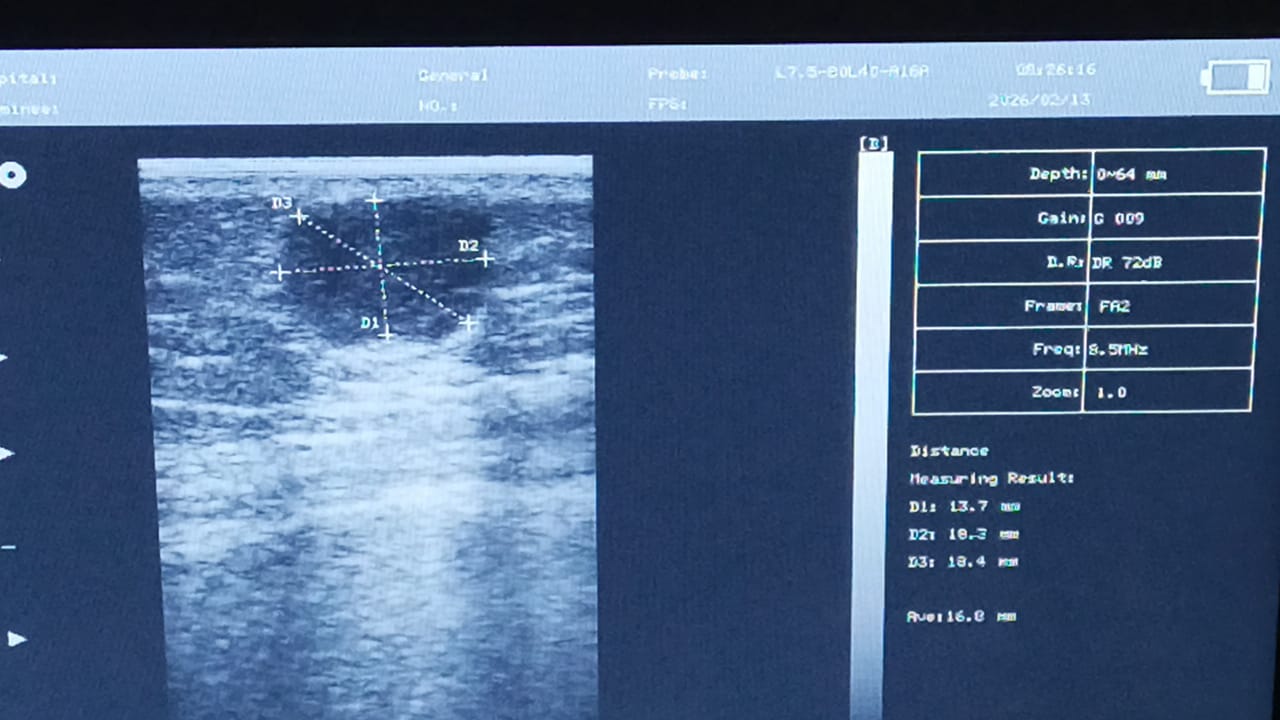

Dr. Aníbal Domínguez

Ecografía CMS600P2

Utilizando el ecógrafo para mis evaluaciones previas a cirugías menores. La calidad de imagen es excepcional y me permite medir con exactitud las lesiones. Gran inversión para mi práctica diaria.

CMS600P2 - Ecógrafo Portátil